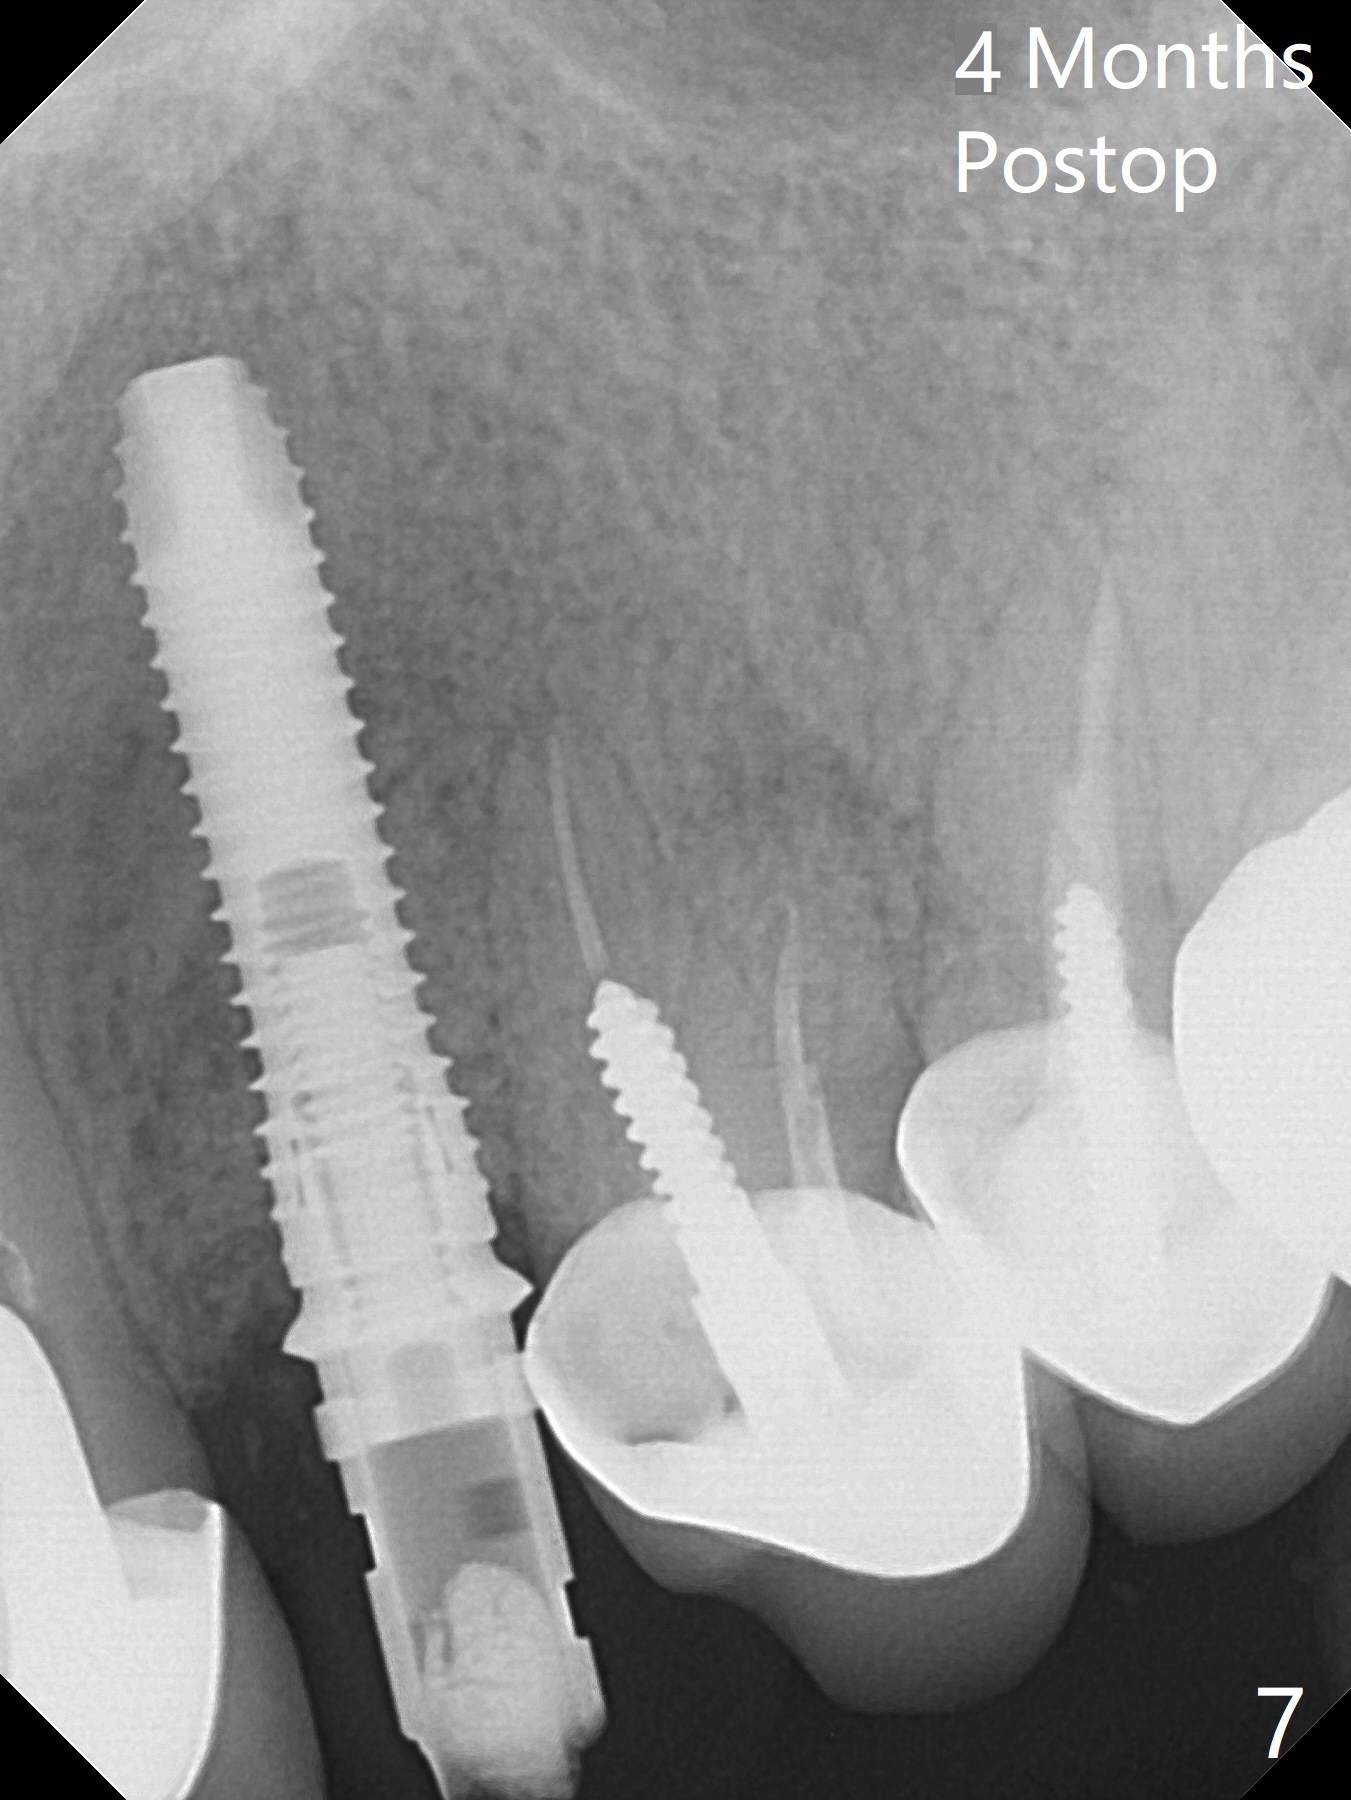

In spite of severe apical infection (Fig1,2 *), a thin narrow strip of the buccal plate (arrowheads, corresponding to the keratinized gingiva) is present when the tooth #11 is extracted. The thin bone keeps the bulging alveolus, i.e., reservoir for bone graft (Vanilla/Osteogen Fig.4 *) after placement of a 3.8x16 mm implant (Fig.3,4). A 4.5x1 mm temporary abutment, placed and trimmed for an immediate provisional, seems to be short in cuff. When an implant is placed deep to prevent periimplantitis, the cuff should be longer, i.e., 3 mm. X-ray should be taken for the depth confirmation after temporary abutment placement. Eight days postop, the mesial gingiva erythema has subsided (Fig.5 < (P: provisional)), while the apical swelling is no longer tender and most likely due to packed bone graft (*). Panoramic X-ray taken 2 weeks postop shows the clearance from the nasal cavity or the maxillary sinus (Fig.6). While the hard tissue around the implant seems to be healthy 5 months postop (Fig.7), the soft tissue is not (Fig.8). The temporary abutment is changed to a cemented one (4.5x5(2) mm) for impression (Fig.8). Since the neighboring crowns are PFM (Fig.6), the new crown will be made of the same material for shade match. Indeed PFM helps shade match in this case as well (Fig.9,10). Switching abutments (from temporary to cemented) makes it difficult to seat the crown. Post cementation X-ray leaves record for future contact loosening. The buccal gingiva remains erythematous associated with open margin (Fig.11 >) 1 year 4 months post cementation. There is no obvious bone loss 1 year 4 months post cementation (Fig.12). It appears that the crown and abutment need to be changed. Although the gingival margin remains erythematous, the gingival hemorrhage is basically lacking due to better oral hygiene during Shelter at Home (1 year 9 months post cementation, Fig.13). Change in abutment and crown will be conducted post coronavirus pandemic. In fact the abutment is incompletely seated (Fig.14 <). In addition, the tooth #12 is symptomatic with PARL associated with the buccal root (*). CBCT indicates possible buccal root fracture (Fig.15,16 ^) and loss of the buccal plate (Fig.16 <).